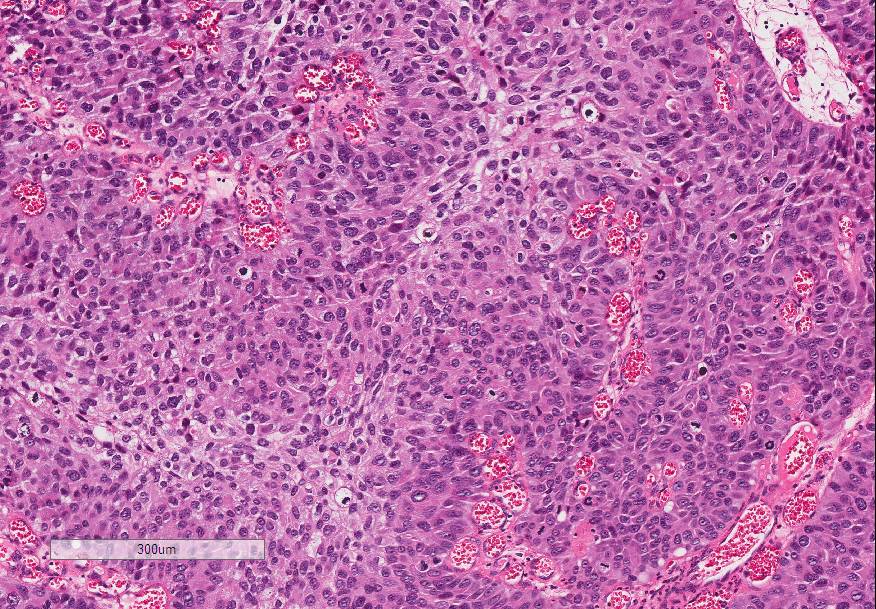

Bladder Papillary Lesions

Case ID: 646